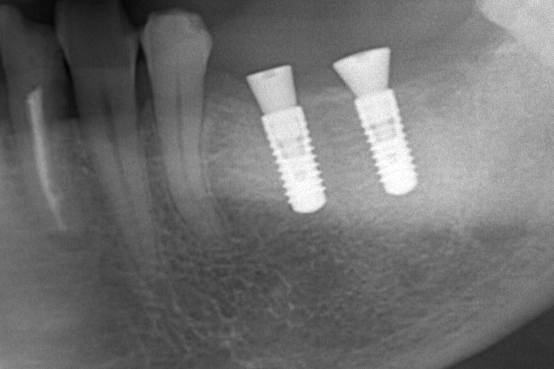

インプラント

重度虫歯からのインプラント・入れ歯治療(*^-^*)